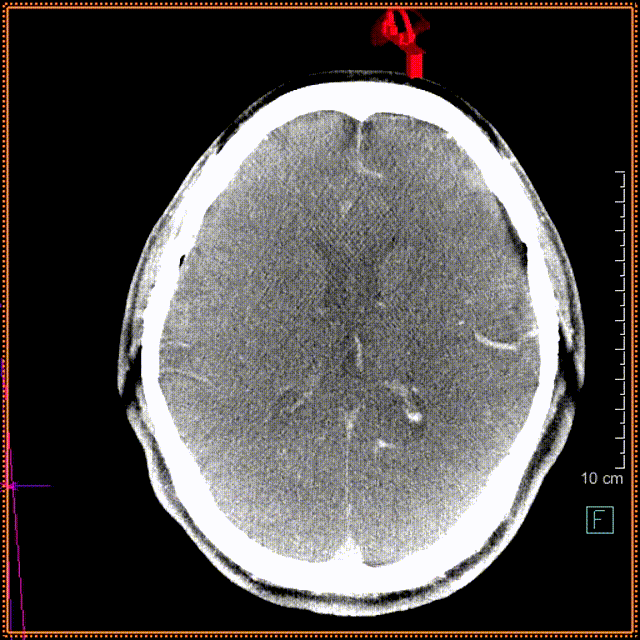

头颅CT

现病史:2月前无明显诱因开始出现发作性头痛,伴有视物模糊感,无肢体活动障碍。对症治疗后未见缓解,门诊头颅CT检查提示“大脑前动脉动脉瘤”收入我科。

初步诊断:大脑前动脉动脉瘤。

位置:左侧大脑前动脉动脉瘤。